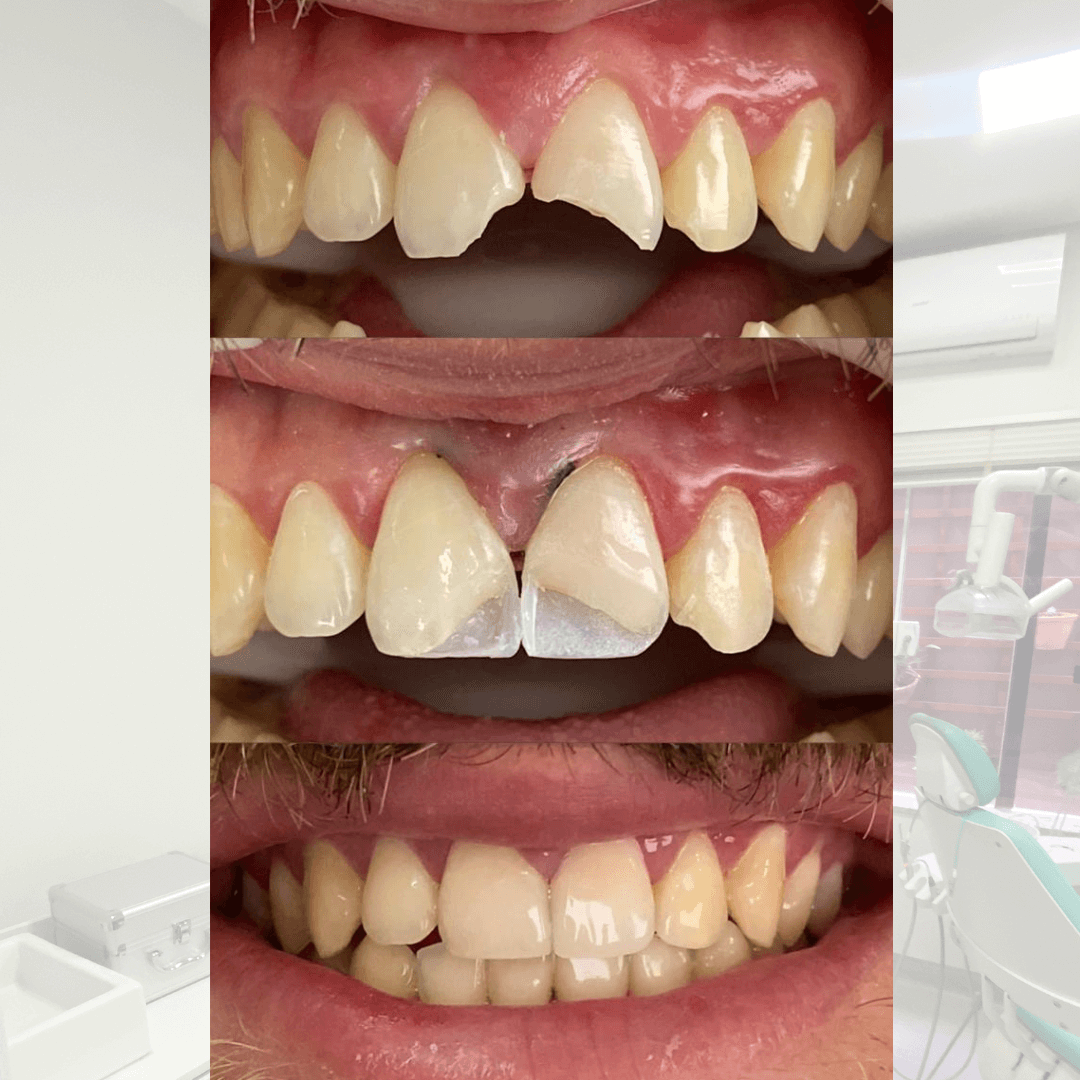

Tenho forte afinidade pela Endodontia, além de ampla experiência em reconstrução de dentes severamente destruídos e restaurações estéticas.

Meu foco é claro: salvar, restaurar e devolver confiança a cada sorriso com técnica, sensibilidade e precisão.